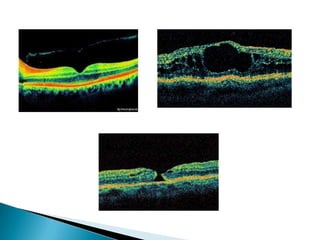

   OCT it is non invasive noncontact imaging

that produce high resolution cross sectional

image

   Useful in diagnosing macular disorders and

to delineate retinal layers and detect subtle

anatomical changes

OCT it is non invasive noncontact imaging that produce high resolution cross sectional image  Useful in diagnosing macular disorders and to delineate retinal layers and detect subtle anatomical changes